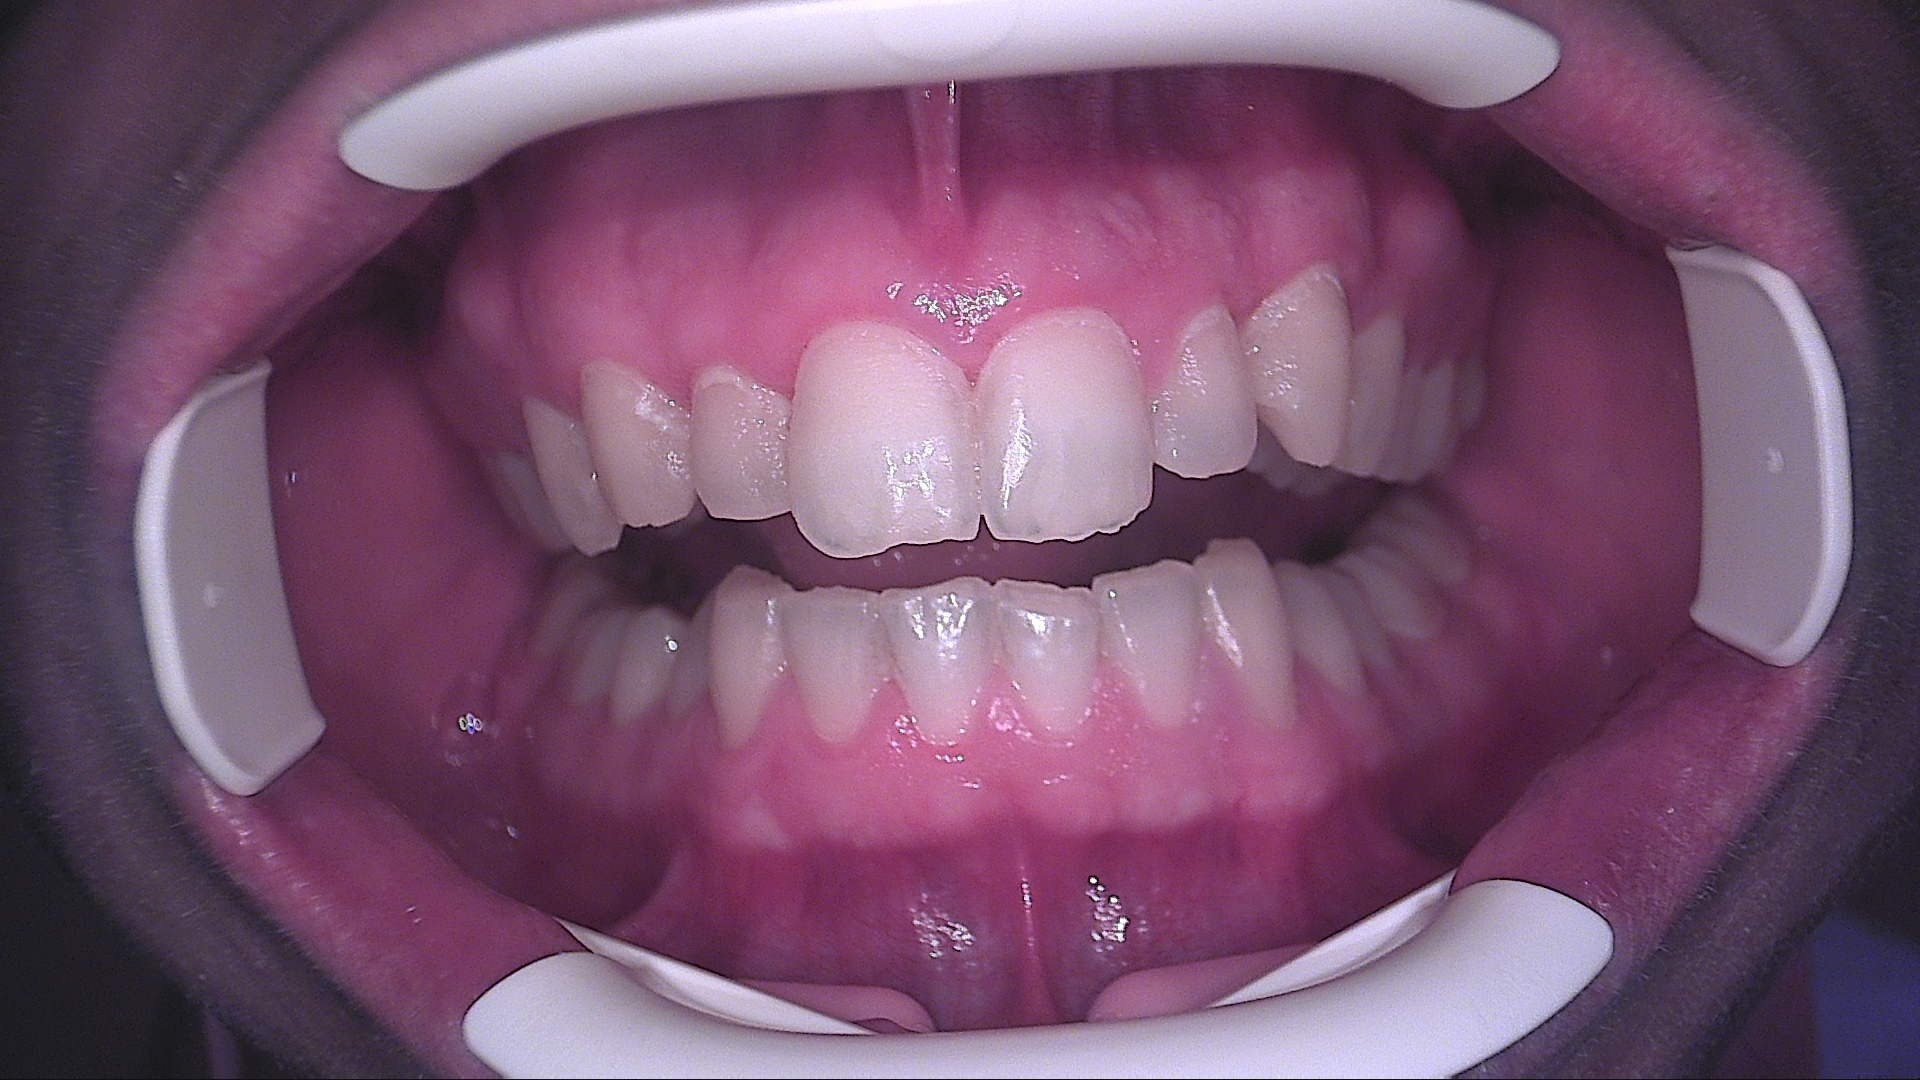

Paziente maschio, 25 anni, militare, riferisce fastidio estetico causato dalla presenza di aree bianche opache persistenti sugli incisivi superiori. All’esame

obiettivo in luce bianca si osservano white spot a livello degli elementi 11, 12, 21 e 22. L’esame in fluorescenza con QrayCam Pro conferma la presenza di zone a ridotta mineralizzazione con perdita di fluorescenza compresa tra –47,8% e –56,1% e area di white spot fino a 4007 px².

Fig. 1A - Situazione iniziale in luce bianca: aree bianche opache su 11, 12, 21 e 22.